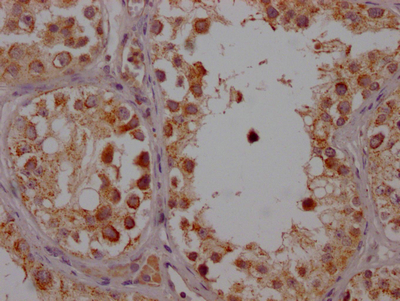

IHC image of CSB-RA554990A0HU diluted at 1:100 and staining in paraffin-embedded human testis tissue performed on a Leica BondTM system. After dewaxing and hydration, antigen retrieval was mediated by high pressure in a citrate buffer (pH 6.0). Section was blocked with 10% normal goat serum 30min at RT. Then primary antibody (1% BSA) was incubated at 4℃ overnight. The primary is detected by a Goat anti-rabbit IgG polymer labeled by HRP and visualized using 0.05% DAB.